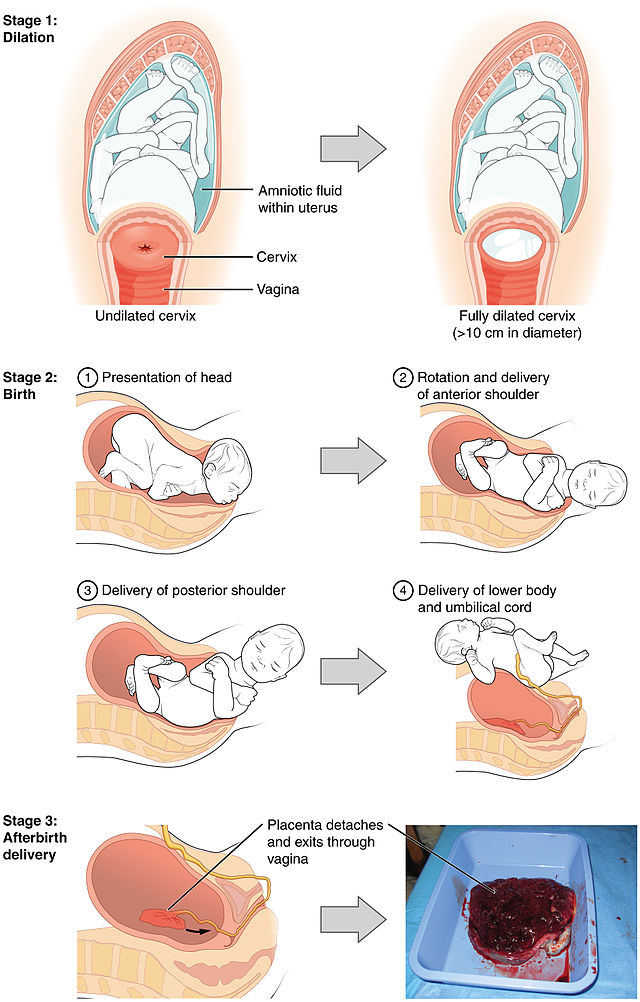

Chapter 10 – Conception, Pregnancy, and Birth – Introduction,

Chapter 10 – Conception, Pregnancy, and Birth – Introduction,![Pelvis with Pregnancy Model, 2 Parts [SKU: MG30131] – Nasco Pelvis with Pregnancy Model, 2 Parts [SKU: MG30131] – Nasco](https://shop.nascohealthcare.com/cdn/shop/files/SR20_535x.jpg) Pelvis with Pregnancy Model, 2 Parts [SKU: MG30131] – Nasco,

Pelvis with Pregnancy Model, 2 Parts [SKU: MG30131] – Nasco, Chapter 10 – Conception, Pregnancy, and Birth – Introduction,

Chapter 10 – Conception, Pregnancy, and Birth – Introduction,![Pelvis with Pregnancy Model, 2 Parts [SKU: MG30131] – Nasco Pelvis with Pregnancy Model, 2 Parts [SKU: MG30131] – Nasco](https://shop.nascohealthcare.com/cdn/shop/files/SR20-04_400x@2x.jpg) Pelvis with Pregnancy Model, 2 Parts [SKU: MG30131] – Nasco,

Pelvis with Pregnancy Model, 2 Parts [SKU: MG30131] – Nasco, Chapter 10 – Conception, Pregnancy, and Birth – Introduction

Chapter 10 – Conception, Pregnancy, and Birth – IntroductionCreating Beautiful Boxes With Inlay Techniques (shin